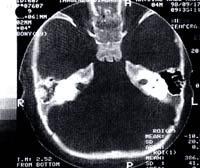

En ningún caso se produjo la necrosis total del colgajo. En cuatro casos existió una dehiscencia de sutura por necrosis parcial que cicatrizó por segunda intención. En los restantes 19 casos existió un cierre primario del defecto. Los resultados funcionales son excelentes así como los estéticos. La mucosa epiteliza rápidamente sobre la fascia y resulta muy dificil diferenciarla del resto de la mucosa de la cavidad oral (Figuras 4 y 5).

Figura 4. Imagenes de TAC donde se observa la reconstruccion del seno maxilar y el paladar.